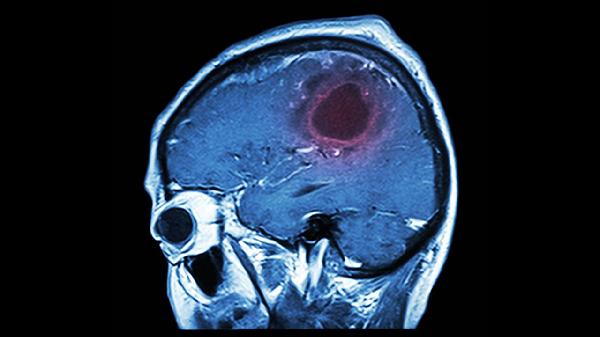

持续一个月以上的梦境重现暴力场景,伴随日间记忆力下降或情绪失控,需排查癫痫、帕金森病等神经系统病变。睡眠监测显示快速眼动期占比超过30%,或出现梦游、尖叫等异常行为时,应及时到神经内科进行多导睡眠图检查。